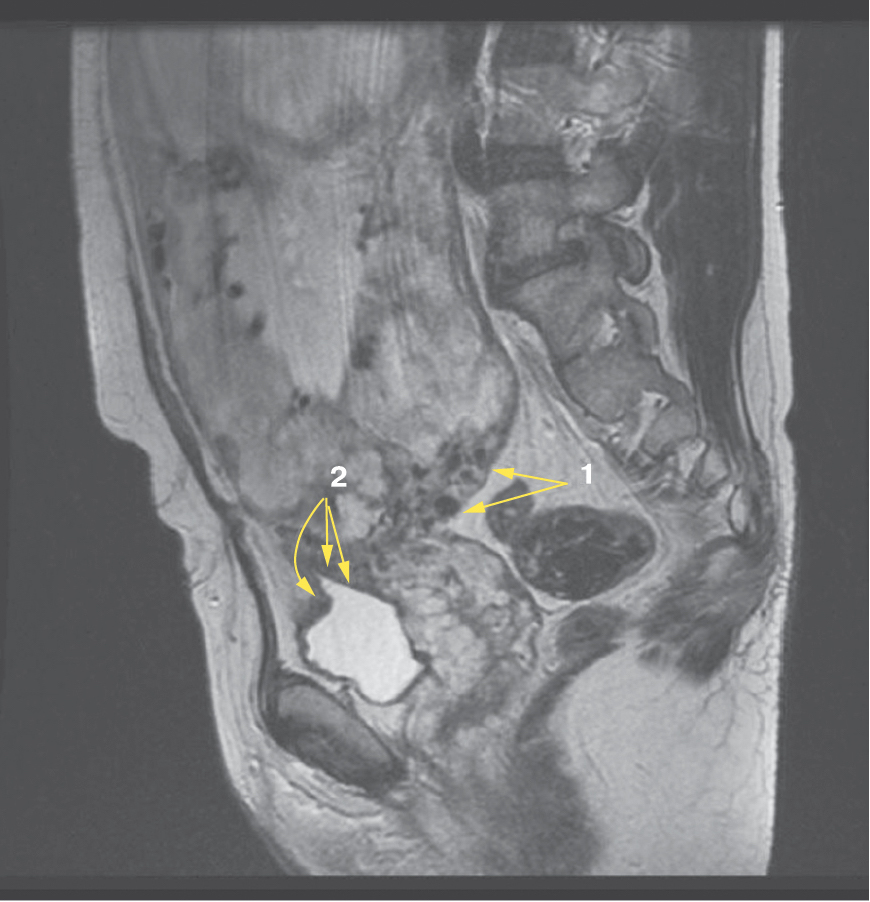

Также стоит выделить особый тип плацентарной гиперваскуляризации, а именно включение в плацентарной ткани изменений по типу «обнаженного сосуда» (рис. 1, 2). Мы провели анализ встречаемости данного признака среди наших пациентов. Любопытным наблюдением явилось то, что данный симптом в нашей выборке встречался только при наличии placenta percreta – 6 случаев, а именно при поражении параметриев, и не встречался при плацентарной инвазии, ограниченной миометрием. «Мостовидные сосуды» были менее специфичны, тем не менее, их наличие также сопровождало тяжелые формы врастания, обусловленные более глубокой инвазией ворсин хориона, – 8 случаев.

Рис. 1. МРТ placenta percreta, симптом «обнаженного сосуда»

Рис. 2. МРТ placenta percreta, симптом «обнаженного сосуда»

Является ли симптом «обнаженного сосуда» патогномоничным для параметральной инвазии или нет, еще предстоит выяснить; однако в ходе исследования установлена его связь с частотой гистерэктомий в группах с наличием симптома «обнаженного сосуда», что, вероятно, обусловлено мощной сосудистой сетью коллатералей и неоангиогенезом. Во всех случаях обнаружения данного признака впоследствии была выполнена вынужденная гистерэктомия (рис. 3–6, пациентка Н., 37 лет).